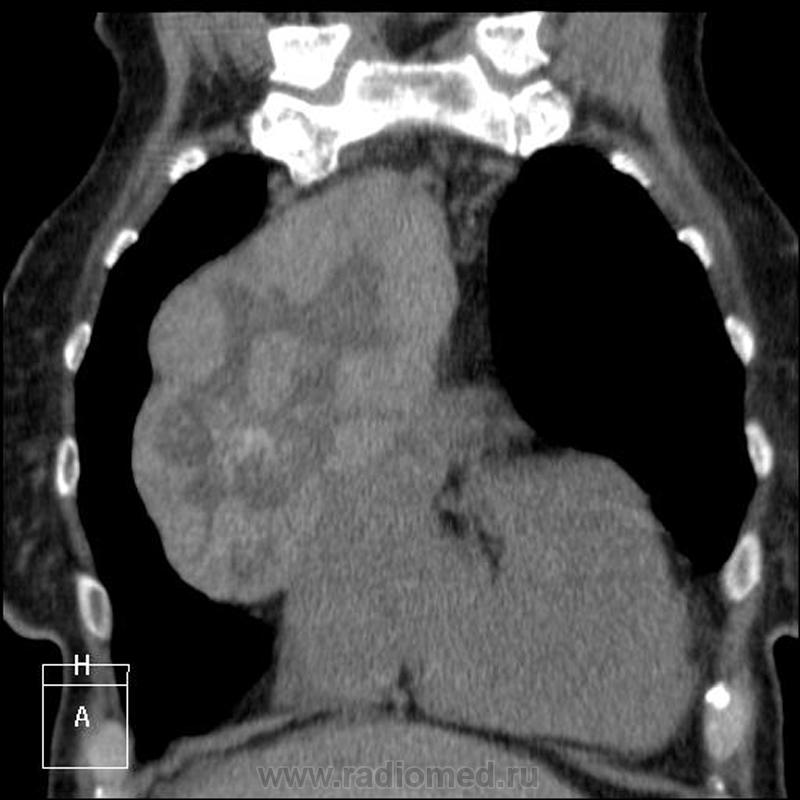

Пациентке 79 лет. Заказана рентгенография ОГК перед операцией (механическая желтуха, камень холедоха). Что скажете, уважаемые коллеги?

Думаю, что интригу с таким какчеством репродукций не создать. Так что пошла закачивать КТшки. Пациентка уже лечилась в мае 2011 по поводу ЖКБ. Тогда же выявлено образование средостения, динамики от сегодняшнего снимка нет. Сколько лет не проходила ФЛГ - неизвестно. Исследования ОГК проводились не мной, разрешение на демонстрацию КТ любезно предоставленно моим коллегой.

До КТ по обзорному снимку в передней прямой проекции - тимома (бугристые, четкие контуры). По боковому - тератома (овальной формы, контуры четкие, ровные, соответствуещее положение). После КТ - тератома (неоднородная структура, плотные включения высокой интенсивности). Думаю еще об одной патологии, но слишком низко расположена. Был хороший повод ещё раз прочитать пособие, вспомнить средостение и т.д. Девиз: больной...книга...анализ...больной в действии. С уважением Nik

И поговорим)): расширение верхнего средостения+бугристая здоровая такая штука в переднем средостении от дуги аорты до 5-го переднего межреберья. Что в сумме получается?

Загрудинный здоровенный зоб...осталось увидеть только перешеек, связывающий его с основной массой щитовидки....

А что, вариант интересный, "оно" 18х9х7 см ниже кажущегося или имеющегося перешейка. Но это не почечная паренхима, ИМХО)). Я могу судить только по структуре и плотности, раз не было контрастирования. И назвала "это" диффузно-узловым зобом с загрудинным распространением. Довольно трудно судить без контрастирования, без верификации, но я свой выбор сделала)). Пара картинок и к вечеру закачаю видео - может, еще идеи возникнут? Или ясности прибавится

Собственно, если быть уж до конца академичным - тогда это не загрудинный зоб, а ВНУТРИГРУДНОЙ зоб, такое в классификации тоже сеть.

Я клоню к тому же: здесь два узла. И за- и внутри-.

Скиалогически - да, два узла; если это зоб, то - внутригрудной (что без загрудинного невозможно даже теоретически

); если два образования, то загрудинный зоб+ неизвестное новообразование переднего средостения. Как верифицировать, вот в чем вопрос?

Еще дело в том, что эти два образования, щитовидную железу и очень сходное по структуре внутригрудное (Вы правы, не загрудинный) образование, разделяют сосуды, и как мне показалось, связь в виде перешейка имеется. Но, наверное, не настолько это и важно. Пока видео не работает, там эту связь можно проследить.